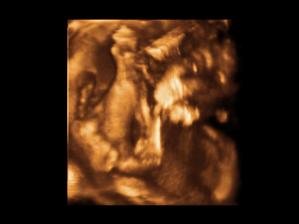

Nas anjelik Alex

Zatial este schovany v brusku ale uz coskoro sa z neho potesime aj nazivo 🙂) Lubime nasho Alexa uz od sameho zaciatku 🙂